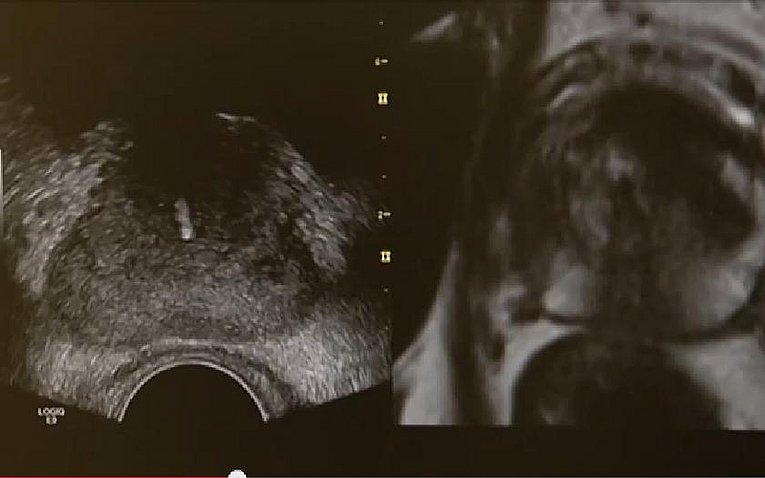

Sonografisch-Kernspintomografie fusionierte Prostatastanzbiopsie:

Um Prostatakrebs frühzeitig zu erkennen und behandeln zu können, gibt es am Universitätsklinikum Erlangen seit diesem Jahr ein neues, hochmodernes Verfahren der Prostatabiopsie. Verglichen mit bisherigen Methoden, kann der Krebs damit früher und sicherer diagnostiziert werden. Prostatakrebs gilt als die häufigste Krebsart bei Männern. Mehr als 60.000 Männer erkranken deutschlandweit jedes Jahr an der bösartigen Tumorerkrankung. Damit ist sie die dritthäufigste Krebstodesursache.